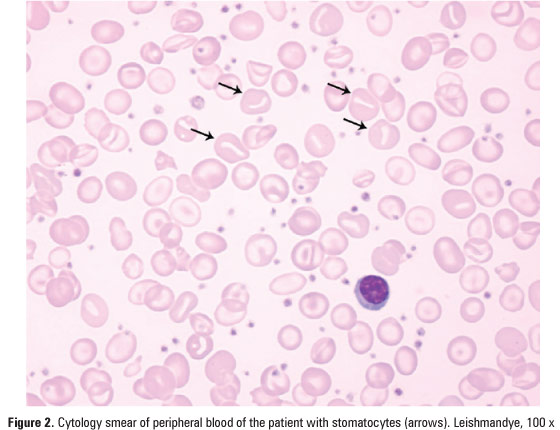

DOI: 10.1590/S1679-45082013000400022

To report a case of iron overload secondary to xerocytosis, a rare disease in a teenager, diagnosed, by T2* magnetic resonance imaging. We report the case of a symptomatic patient with xerocytosis, a ferritin level of 350ng/mL and a significant cardiac iron overload. She was diagnosed by T2* magnetic resonance imaging and received chelation therapy Ektacytometric analysis confirmed the diagnosis of hereditary xerocytosis. Subsequent T2* magnetic resonance imaging demonstrated complete resolution of the iron overload in various organs, as a […]

Keywords: Anemia; Case reports; Chelation therapy; Iron overload; Magnetic resonance imaging